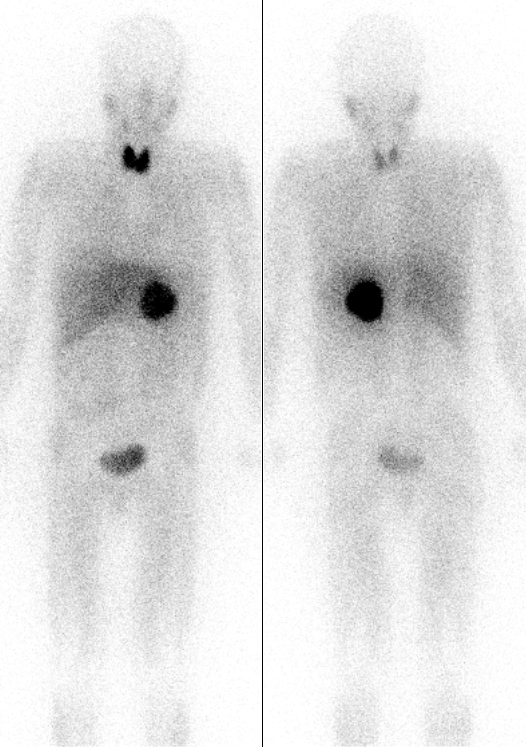

Pheochromocytoma

A particular kind of neuroendocrine tumor (NET) known as a pheochromocytoma develops from chromaffin cells.

Increased 24-hour urine production and serum metanephrine levels are used to diagnose the disease.

Medical excision is used as a treatment of choice.

- 10% located outside of the adrenal medulla such as bladder wall or organ of Zuckerkandl at the inferior mesenteric artery root